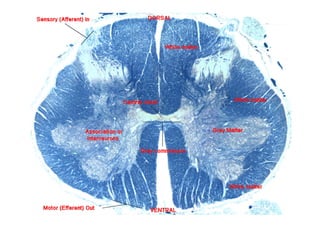

Seções transversais através da

medula espinhal em diferentes

níveis

Organização básica de um nervo espinhal